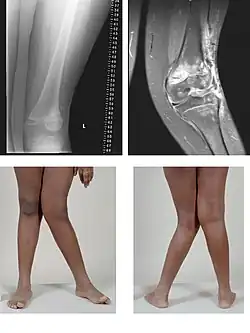

Valgus deformity of the knee (genu valgum), seen in MRI and photograph

• Knee: genu valgum (from Latin genu = knee) – the tibia is turned outward in relation to the femur, resulting in a "knock-kneed" appearance. Common causes of knock-knee in adults include arthritis of the knee and traumatic injuries.